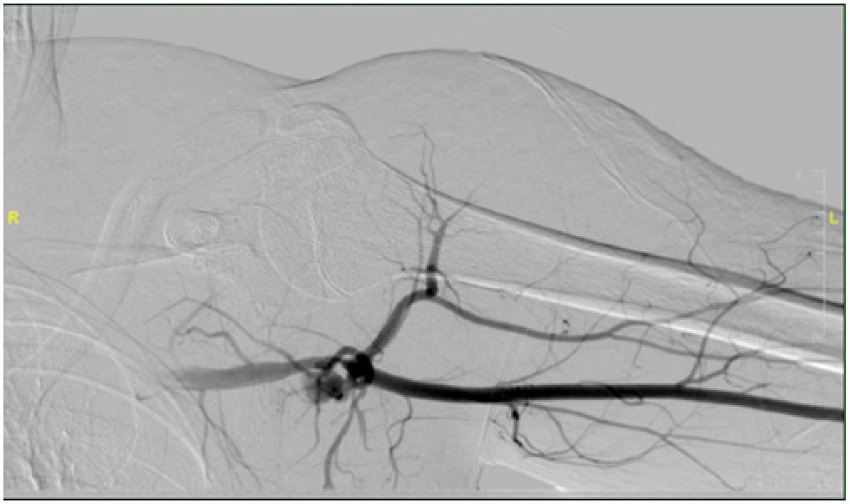

A computed tomography angiogram of the chest revealed a distinct 5 x 5-mm pseudo-aneurysm in the third part of the axillary artery just proximal to the posterior origin of the circumflex humeral artery. A well-defined regional hematoma was adjacent to that segment of the artery, and no active bleeding was noted. The left brachial artery was accessed in the angio suite, confirming the computed tomography findings with diagnostic angiography. Some contrast extraversion was also observed (Figure 1). Using a 7-F sheath, one 6 x 50 mm VIABAHN®-covered stent (W. L. Gore & Associates, Flagstaff, Arizona, USA) was placed over the injury site to cover the origin of the posterior circumflex humeral artery. A 6×100-mm non-compliable balloon was inflated through the stent to ensure complete sealing of the arterial segment. Finally, completion angiography revealed exclusion of the pseudo-aneurism and patent blood flow (Figure 2).